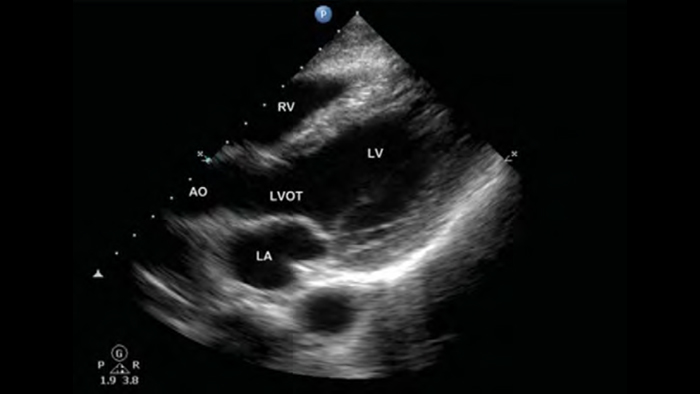

Lleve el ultrasonido a la cabecera del paciente

El uso de Lumify junto a la cama de sus pacientes puede ser una herramienta valiosa para determinar el estado del contenido estomacal y puede reducir el riesgo de aspiración pulmonar. En conjunto, esto puede reducir el riesgo de complicaciones por anestesia.

• Rango extendido de frecuencias de operación de 4 a 1 MHz • 2D, Doppler a color, Modalidad M, XRES avanzado e imágenes armónicas multivariables • Imagenología de alta resolución para aplicaciones abdominales y cardíacas: optimizaciones de preajustes de imágenes cardíacas, gineco-obstétricas, pulmonares, abdominales y FAST.